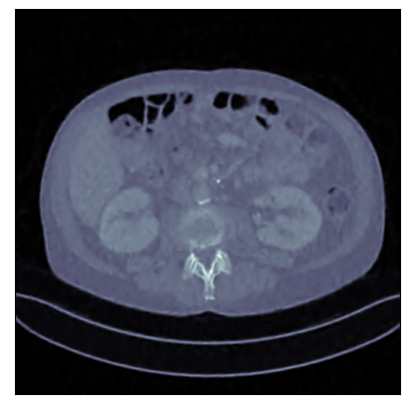

Refer to captionRefer to caption

Ground-truth

FBP: 21.303 dB, 0.195

TV: 31.690 dB, 0.889

U-Net: 36.712 dB, 0.920

LPD: 36.810 dB, 0.912

AR: 36.694 dB, 0.907

ACR: 35.708 dB, 0.897

ACNCR: 36.533 dB, 0.921

AWCR: 37.603 dB, 0.918

AWCR-PD: 37.941 dB, 0.924

Figure 2: Reconstructed images obtained using different methods, along with the associated PSNR and SSIM, for sparse view CT. In this case the AWCR and AWCR-PD achieve the highest PSNR and SSIM. Furthermore, both AWCR methods retain the fine-structure in the reconstruction, unlike the ACNCR and ACR, the only other methods which possess convergence guarantees.

6.2 Computed Tomography (CT)

For evaluation of the proposed methodology, we consider two applications: CT reconstruction with (i) sparse-view and (ii) limited-angle projection. Supervised methods require access to large high-quality datasets for training, but outside of curated datasets, obtaining large amounts of high-quality paired data is unrealistic. For this reason weakly supervised methods are of significant interest for this problem.

We consider two versions of the AWCR method, one using the subgradient method to solve Equation 1.2 and one using PDHGM, denoted AWCR-PD. These are compared with:

• two standard knowledge-driven techniques: filtered back-projection (FBP) and total variation (TV) regularisation, which act as the baseline;

• two supervised data-driven methods: the learned primal-dual (LPD) method [Adler and Öktem, 2018] and U-Net-based post-processing of FBP [Jin et al., 2017], considered to be state of the art methods in end-to-end learned reconstruction from the two main paradigms: algorithm unrolling and learned post-processing;

• three weakly supervised methods: the AR, ACR, and the ACNCR. Adversarial regularisation methods were chosen as the currently best performing, to the authors’ knowledge, weakly supervised methods for CT.

These comparisons illustrate the trade-offs in levels of constraints and supervision versus stability and performance. For details of the experimental set-up, see Section G.1. We measure the performance in terms of the peak signal-to-noise ratio (PSNR) and the structural similarity index (SSIM) [Wang et al., 2004]. We report average test dataset results in Table 1, with further visual examples in Figure 2.

Sparse view CT As in [Lunz et al., 2018] performance of AR during reconstruction begins to deteriorate if the network is over-trained, so early stopping must be employed in training. For the ACR, ACNCR, and both AWCR methods this does not occur due to reduced expressivity, yet both AWCR methods surpass the performace of AR. Indeed, the AWCR-PD method approaches the PSNR accuracy of the strongly supervised U-Net post-processing method.